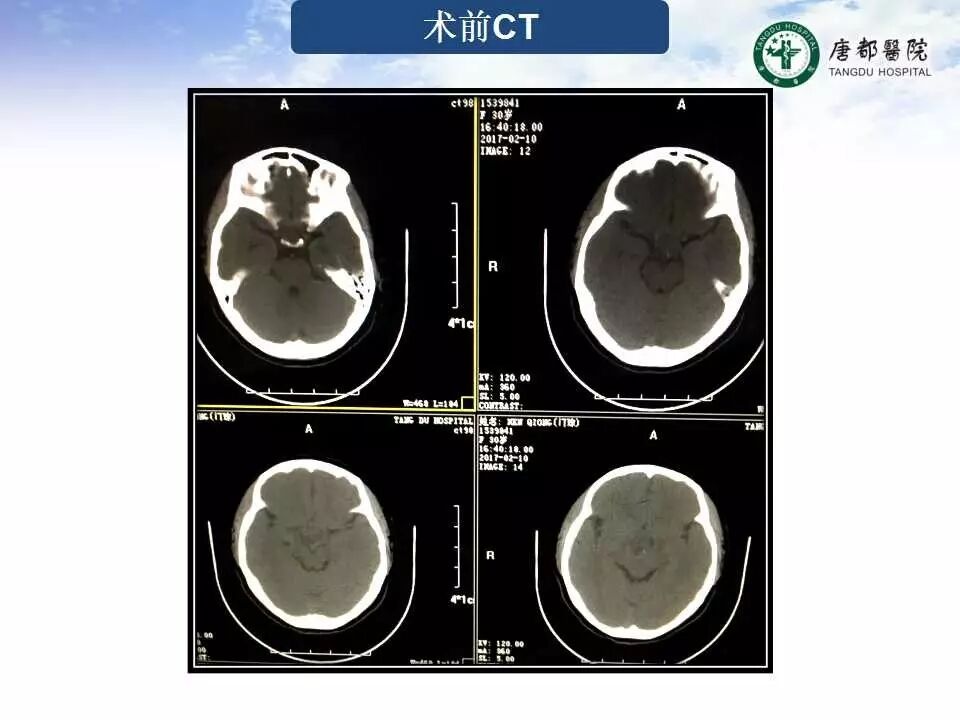

Case 1

长按并识别二维码即可查看该手术视频